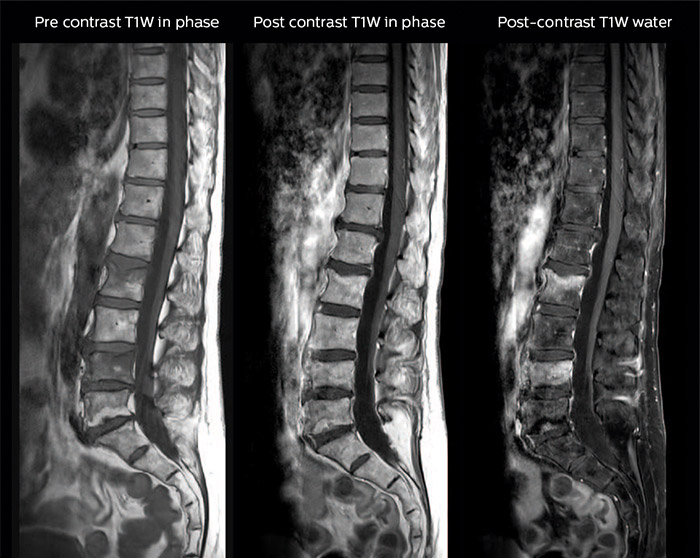

“In our spine cases, we use mDIXON TSE for patients with degenerative and inflammatory spine issues, vertebral fractures and vertebral and paravertebral tumor characterization,” says Dr. Lefebvre. “It provides, in a single acquisition, different contrasts so we can both visualize and characterize spinal, focal or diffuse spine lesions.”

“mDIXON TSE makes real a difference in cases of acute and traumatic spinal injuries, where it allows us to reduce the scan time by only using a limited number of sequences. For patients in pain, who come from the emergency unit and need surgery, for example, MRI must be very fast. With a single T2-weighted acquisition we can assess spinal cord, vertebral disc and ligament wholeness with in-phase images, as well as trabecular fracture and edematous changes with water images.” Dr. Lefebvre cites other frequent examples of spinal diseases that benefit from the mDIXON technique. “In cases of vertebral disc herniation or degenerative discs, for example, we don’t have to choose between fat or no fat images. We can assess morphological changes in the endplate with in-phase images from T2-weighted sequences and in the water image from the same acquisition we will see inflammatory changes into endplates.”